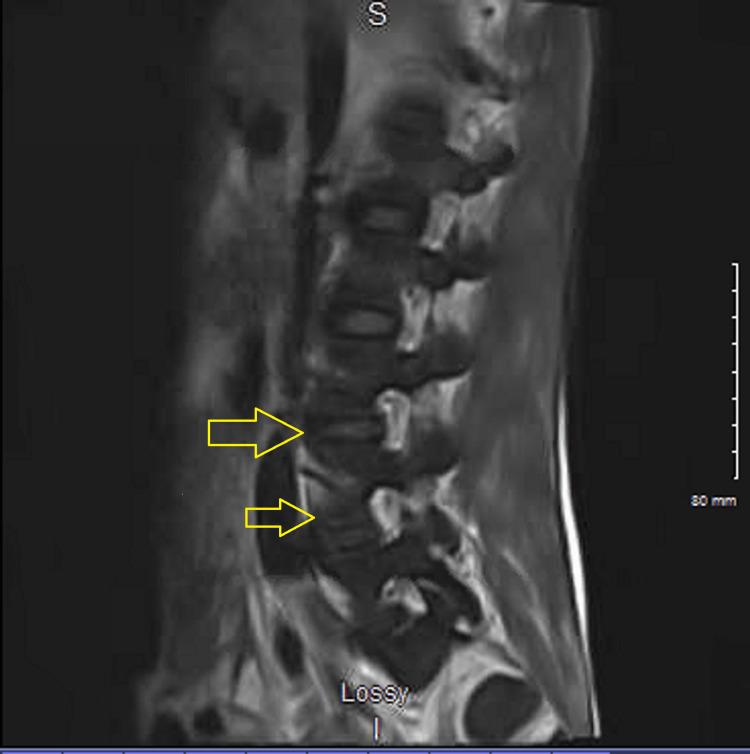

Neurological complications are a significant problem in bacterial endocarditis. Cerebral embolism is the most frequent concern. Acute embolic disease may trigger focal seizures or mycotic aneurysms. Miliary infection is also common, and lumbar puncture can guide in determining the infective organism. Purulent cerebrospinal fluid (CSF) consists often of , a virulent organism, whereas non-virulent organisms (i.e., viridans streptococci) have normal CSF formulae. Microscopic abscesses suggest the potential for aneurysm from bacterial endocarditis amplifying the risk of intracranial hemorrhage. Mannitol and hypertonic (3%) saline are intravenous medications used as a rescue treatment for brain hemorrhage. A patient diagnosed with mycoplasma pneumonia and septic shock secondary to tricuspid endocarditis with extensive pulmonary emboli and metastatic infection to his spine was initiated on antibiotics. He developed a massive intracranial bleed from the rupture of mycotic septic emboli and was given mannitol to decrease intracranial pressure, which caused anaphylaxis.

神经并发症是细菌性心内膜炎中的一个重要问题。脑栓塞是最常见的关注点。急性栓塞性疾病可能引发局灶性癫痫发作或霉菌性动脉瘤。粟粒性感染也很常见,腰椎穿刺有助于确定感染病原体。脓性脑脊液通常由一种毒性很强的病原体引起,而非毒性病原体(如草绿色链球菌)的脑脊液指标正常。显微镜下的脓肿提示细菌性心内膜炎引发动脉瘤的可能性,会增加颅内出血的风险。甘露醇和高渗(3%)盐水是用于脑出血抢救治疗的静脉用药。一名被诊断为支原体肺炎和三尖瓣心内膜炎继发感染性休克、伴有广泛肺栓塞和脊柱转移性感染的患者开始使用抗生素治疗。他因霉菌性脓毒性栓子破裂出现大量颅内出血,并使用甘露醇降低颅内压,但引发了过敏反应。